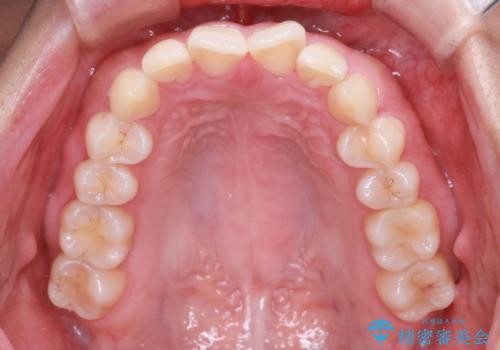

【インビザライン】翼状捻転+出っ歯を治したい

- 前歯の捻れと口元の突出を主訴に来院されました。

インビザラインを用いて上顎の遠心移動を行い、前歯を下げながら凸凹を綺麗に治すことができました。

歯を抜かない矯正治療を行う場合、口元は極端には変わりません。

今回は奥歯の遠心移動を行い、できる限り前歯を下げられるように治療を行いました。